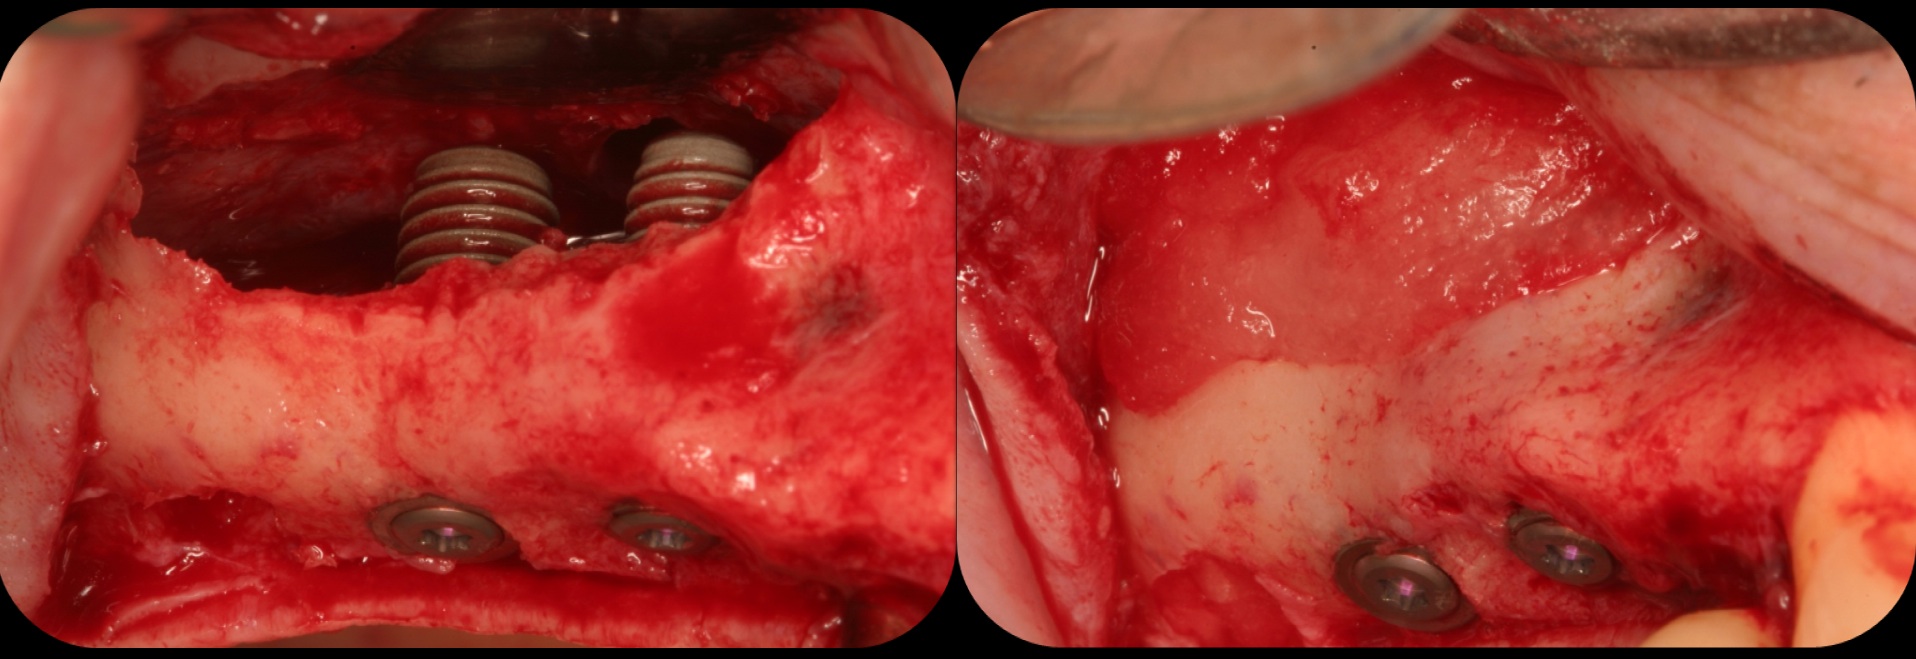

Traditional sinus lift.

Fig. 11

Implants plus BMP without bone graft.

Fig. 12

Bone regeneration and implants loaded in 16 weeks.

Fig. 13

There is also “the Holy Grail” of regeneration, bone morphogenic protein (BMP), whose ability to stimulate the formation of bone where bone does not normally grow was discovered in the mid-60s by orthopedic surgeon Marshall R. Urist, who believed it was destined to bring osteogenesis under the control of surgeons; clinically, this recombinant DNA technology (recombinant human BMPs; rhBMPs) is being used in the regeneration of deficient sites planned for implant placement (Figure 11 through Figure 13).